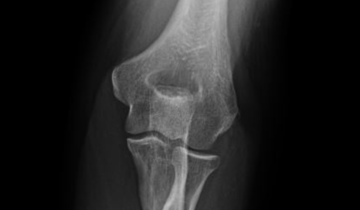

The Extremities

Differential Diagnosis